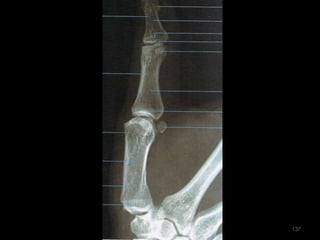

Incidência lateral (lateral-medial ou médio-lateral) dos dedos141

142

143